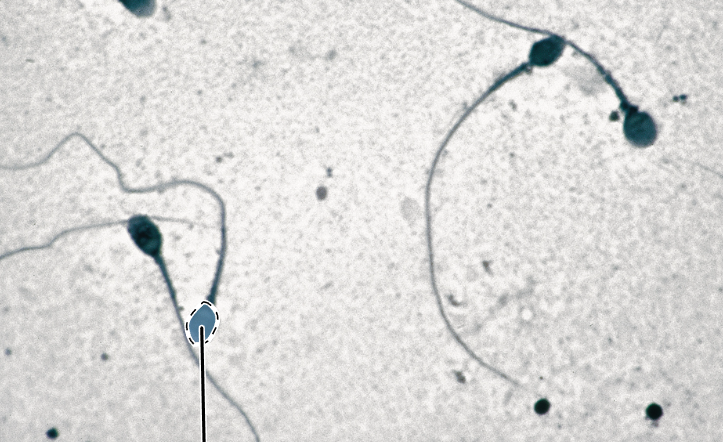

sperm

heads

tails

tail

midpiece

head